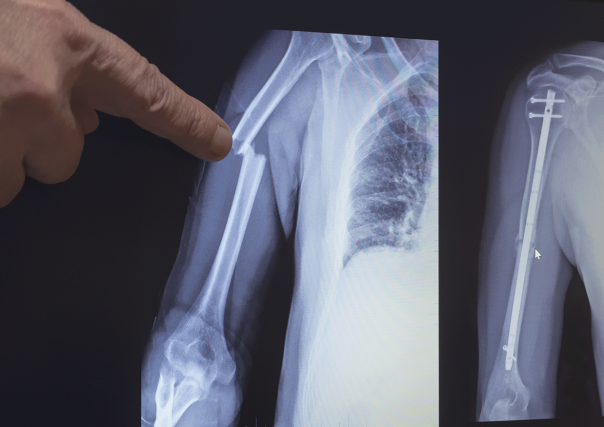

During surgery, the doctor drills a hole into the medullary cavity of a broken bone and then inserts a long titanium IM nail into the hole. The nail is then screwed into place, holding the broken pieces together securely so they can heal properly.